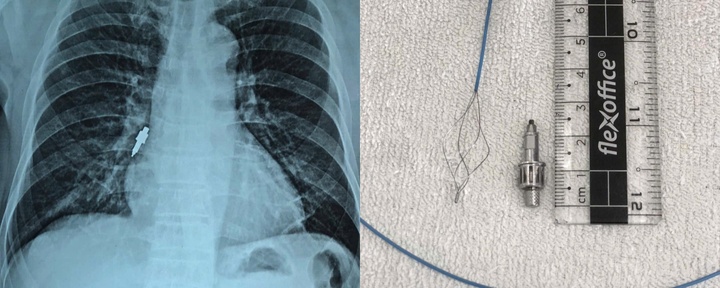

Viên thuốc xách tay mà bệnh nhân dùng. Ảnh: VietNamNet.

Kết quả MRI cho thấy bà T. bị nhồi máu não mới trên nền tổn thương cũ, kèm nhiều ổ vi xuất huyết rải rác. Bệnh nhân sử dụng sản phẩm không rõ nguồn gốc trước đó có thể làm tăng nguy cơ xuất huyết, khiến bệnh cảnh thêm phức tạp.